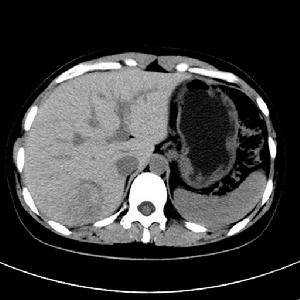

CT:平掃為低密度或等密度占位,有1/3的病人在腫塊中央可見低密度星狀瘢痕;89%~100%病變增強後動脈期即出現快速、顯著、均勻的強化,中央瘢痕為低密度或輕微高密度,延遲期多數病灶為等密度,中央瘢痕可呈等密度或高密度。MRI:除瘢痕信號均勻,T1WI為等信號或稍低信號,T2WI為等或稍高信號;注射Gd-DTPA後有兩種典型的動態增強方式:①無瘢痕的FNH在動脈期明顯增強、門靜脈期和延遲期輕至中度增強或呈等或稍低信號;②有瘢痕的FNH在動脈期明顯增強(瘢痕無增強)、門靜脈期輕至中度增強或呈等或稍低信號、門靜脈和延遲期瘢痕逐漸增強。FNH不典型影像表現有多發病灶、存在假包膜、無瘢痕、出血和不均勻增強等。約有50%的病人可見中央瘢痕,其T1加權相為低信號,T2加權期高信號。超順磁性物質,靶細胞分別為Kuffer細胞和肝細胞,這些造影劑可以用來證實肝細胞源性病變,當FNH病灶內的Kuffer細胞攝取造影劑後在T2加權相使信號強度降低。血管造影:FNH顯示為多血管腫塊,表現為中央動脈供血並向周邊放射性灌注,肝實質期染色均勻,門靜脈期呈現充盈缺損,病變不侵犯門靜脈,無血管滲漏及動靜脈瘺。核素檢查:採用99mTc硫膠閃爍照相,有50%~70%的FNH顯示硫膠濃集,可與不含Kuffer細胞的肝癌、肝腺瘤等鑑別。